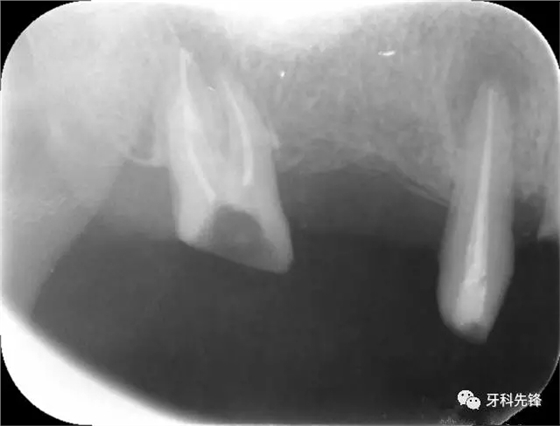

圖1術(shù)前X光片

X 示:15 根管透射,根尖有陰影

14根管阻射,恰填,無異常

46 根管阻射,恰填,根分叉骨密度降低,近中根尖陰影較大

圖8治療術(shù)后X光片

圖1814 15 三個(gè)月后X光片(根尖陰影減?。?p style="text-align: left;">640.webp (22).jpg